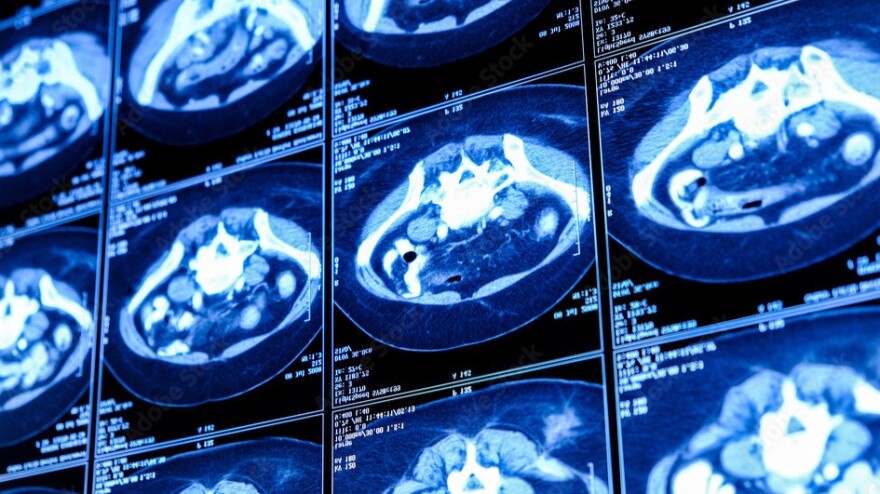

Chụp CT toàn thân có hiệu quả trong việc phát hiện ung thư không?

Một số trung tâm hình ảnh và y tế đã bắt đầu cung cấp dịch vụ chụp CT toàn thân như một phương pháp phát hiện sớm ung thư dành cho những người khỏe mạnh không có triệu chứng liên quan đến ung thư. Nhưng liệu những rủi ro của việc chụp CT toàn thân có vượt qua được lợi ích tiềm năng hay không?